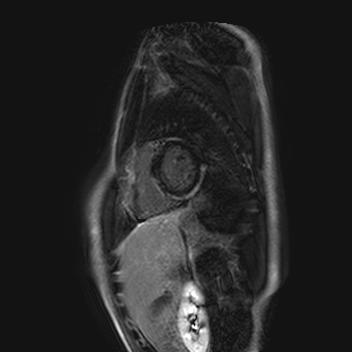

Mladý muž byl poprvé hospitalizovaný v roce 2016 ve věku 17 let pro několik dní trvající bolesti na hrudi bez souvislosti s virovým onemocněním. Vstupní vyšetření prokázala na EKG elevace úseku ST ve svodech II, III, aVF (obr.1), elevaci kardiomarkerů (troponin T 1 756 ng/l), mírné zvýšení C-reaktivního proteinu (CRP;13,8 mg/l), nebyla přítomna leukocytóza. V dalším průběhu hospitalizace byla doplněna transtorakální echokardiografie a CT koronarografie s normálním nálezem. Dále byla provedena sérologická vyšetření na přítomnost kardiotropních virů, atypických bakterií a borrelií a autoimunitní vyšetření, všechnas negativním nálezem. Diagnózu suspektní akutní myokarditidy podpořilo vyšetření magnetickou rezonancí s průkazem edému v oblasti spodní stěny, laterální stěny a septakomor v bazálních a středních segmentech v T2-váženém obraze (obr. 2) a známky pozdního sycení epikardiálně v odpovídajících oblastech (obr. 3).

V průběhu dalších osmilet následovalo pěthospitalizací s podobným průběhem. S bolestmi na hrudi, elevací kardiomarkerů, normálním echokardiografickýmnálezem a stacionárním nálezem neischemického postkontrastního sycení na magnetické rezonanci (obr.4). Během třetíhospitalizace v červnu 2021byla zachycena komorová extrasystolie morfologie blokády pravého Tawarova raménka (RBBB). V rámci diferenciální diagnostikybylo pomýšleno na arytmogenní kardiomyopatii levékomory a doplněno genetické vyšetření,které prokázalo patogenní variantu v genu pro desmoplakin ((6p24.3)c4518del).Diagnóza byla potvrzena a opakované ataky suspektní z akutní myokarditidy přehodnoceny jako hot fáze základního onemocnění.V rámci hospitalizace v únoru 2022 byl pacientovi implantován smyčkový záznamník („looprecorder“). Následně byly dokumentovány nesetrvalé komorové tachykardie a v květnu téhož roku pacient podstoupil implantaci ICD v primární prevenci náhlé srdeční smrti. Poslední ataka hot fáze arytmogenní kardiomyopatie levé komory proběhla v září roku 2024. Dle ambulantní kontroly v listopadu 2024 byl přítomen echokardiograficky zcela normální nález a nebyla alterována ani deformace myokardu při hodnocení globálního longitudinálního strainu levé komory. Nemocný byl bez známek kardiální insuficience a byl asymptomatický. V lednu 2025 bylo doplněno kontrolní vyšetření magnetickou rezonancí, dle kterého je nadále přítomna zachovaná regionální i celková systolická funkce levé komory a prstencovité sycení subepikardiálně až midmyokardiálně s mírnou progresí nálezu v oblasti septa komor. Nadále přetrvává normální regionální i celková systolická funkce pravé komory s absencí pozdního postkontrastního sycení pravé komory. V rámci rodinného screeningu byla prokázána identická patogenní varianta v genu pro desmoplakin u otce a bratra nemocného.

Obr. 4 – MR: neischemické pozdní sycení, 2021